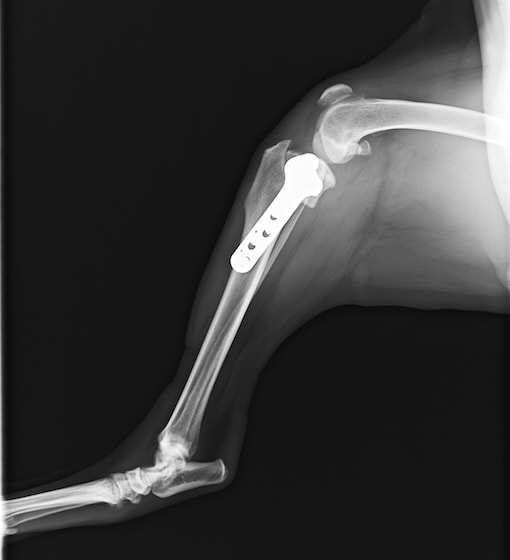

前十字靱帯断裂症例(2025/02/06)

HPの外科の前十字靱帯断裂のページに、犬のTPLO(脛骨高平部水平化骨切り術)手術を行った症例を追加致しました。大腿骨と脛骨を繋ぐ靱帯の一つである前十字靱帯が断裂すると、膝の関節が不安定となり関節炎が進行します。また膝関節内のクッションの役割を果たしている半月板にもダメージが加わり、痛みを生じて正常な歩行が出来なくなります。治療法としては術後の機能回復の早さから、近年ではTPLO法(脛骨の一部を円形に切り、角度を調整し膝関節を安定化させる手術)が多く選択されています。前十字靭帯断裂は中高齢犬によく見られる病気であり、膝蓋骨脱臼に併発することもあります。気になる症状がある場合はお早めにご相談下さい。

症例報告(2024/08/27)

外科の前十字靱帯断裂のページに、犬のTPLO(脛骨高平部水平化骨切り術)手術を行った症例を追加致しました。大腿骨と脛骨を繋ぐ靱帯の一つである前十字靱帯が断裂すると膝の関節が不安定となり関節炎が進行します。また、膝関節においてクッションの役割を果たしている半月板にもダメージが加わり、痛みを生じて正常な歩行が出来なくなります。治療として多くの場合手術が選択されますが、術後の回復の早さなどから近年ではTPLO法(脛骨の一部を切り角度を調整し膝関節を安定化させる手術)が多く選択されています。

犬のTPLO(脛骨高平部水平化骨切り術)手術(2024/08/07)

外科の前十字靱帯断裂のページに、犬のTPLO(脛骨高平部水平化骨切り術)手術を行った症例を追加致しました。大腿骨と脛骨を繋ぐ靱帯の一つである前十字靱帯は、断裂すると膝の関節が不安定となり関節炎が進行し、またクッションの役割を果たしている半月板にもダメージが加わることで、痛みを生じて正常な歩行が出来なくなります。治療として多くの場合手術が選択されますが、術後の回復の早さなどから近年ではTPLO法(脛骨の一部を切り角度を調整し膝関節を安定化させる手術)が多く選択されています。